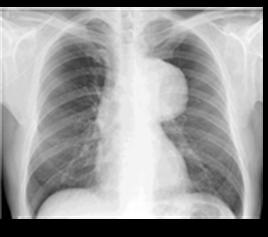

Hallazgos de la radiografía de tórax que sugieren una lesión aórtica cerrada (lesión de grandes vasos)

♦ Ensanchamiento mediastino (RX supino > 8 cm; RX vertical > 6 cm)

♦ Obliteración botón aórtico

♦ Desviación tráquea o sonda nasogástrica a la derecha

♦ Fractura primeras costillas

♦ Fractura de escápula

♦ Hemotórax izquierdo masivo

♦ Desviación del bronquio principal derecho hacia abajo

Figura 31. La radiografía de tórax (A) muestra un mediastino ensanchado después de una lesión contusa en el tórax (flechas). Figura 32. El aortograma en proyección anteroposterior (B) muestra un desgarro circunferencial del istmo (flecha). Se observa un pequeño pseudoaneurisma en el sitio de inserción del ligamento arterioso (punta de flecha).